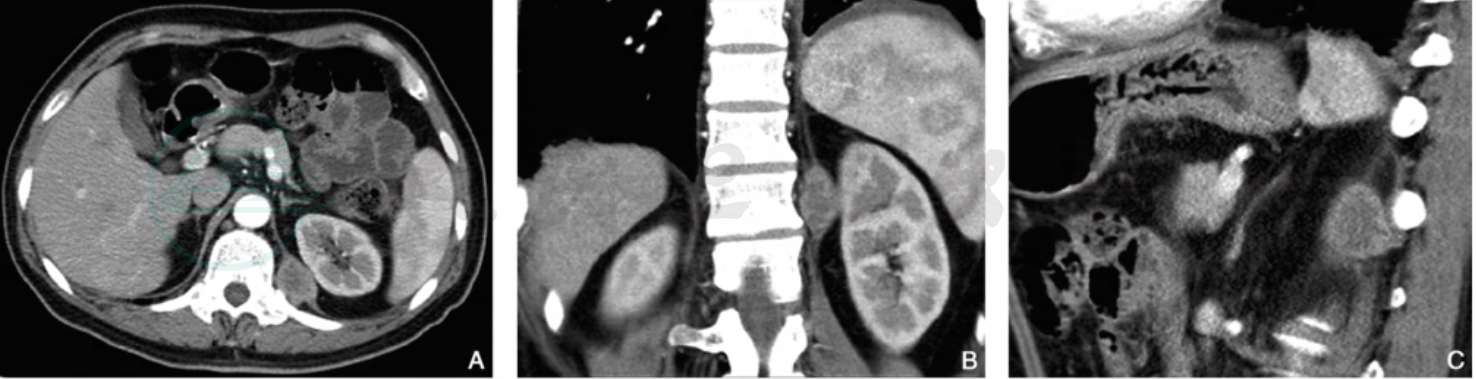

图3 膈肌转移瘤、肝脏转移瘤(肺癌)

注:男性,56岁,CT增强横断面动脉期(A)及静脉期(D)示左侧膈肌脚有一类椭圆形结节影,密度不均,冠状位重建动脉期(B)、静脉期(E)及矢状位重建(C)、静脉期(F)显示结节与膈肌脚关系;此外,肝右叶下段可见一小转移瘤结节。